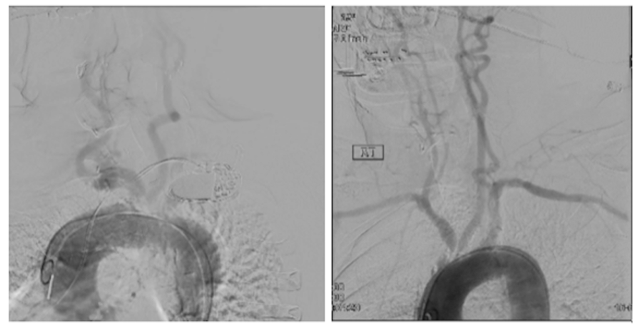

An 82-year-old man with a medical history of coronary artery disease (CAD) status post coronary artery bypass grafting and percutaneous intervention (PCI), peripheral arterial disease (PAD), hypertension, sick sinus syndrome with a permanent pacemaker, and paroxysmal atrial fibrillation presented with more than 6 months of lightheadedness and loss of balance. A computed tomography (CT) angiogram revealed 70% to 75% stenosis at the proximal segment of the left internal carotid artery (ICA) at bifurcation and the ostial common carotid artery (CCA), 99% subclavian artery stenosis, and a heavily calcified type 3 aortic arch (Figure 1). Given the ostial location, degree of calcification, and severe angulation related to a type 3 arch, a retrograde approach was favored over the traditional transfemoral route due to concerns about safe catheter and wire maneuverability. Treatment was planned with a hybrid approach, where a vascular surgeon and interventional cardiologist worked in tandem. In a multistage procedure, the patient first underwent stenting of a left sub-totally occluded subclavian artery via a transfemoral approach. Three weeks later, he returned for a hybrid procedure. Under general anesthesia, the vascular surgeon first performed the carotid cutdown. Neuroprotection was achieved using distal clamping of the ICA and external carotid artery. Following standard heparinization, a short 6Fr sheath was placed in a retrograde manner over a 0.35” Supra Core wire (Abbott) (Figure 2). Afterwards, the patient underwent a typical carotid endarterectomy (CEA) by CT surgery.

The second patient was a 72-year-old-woman with medical history of CAD status post PCI, PAD, and chronic obstructive pulmonary disease who presented with 6 months of dizziness, presyncope, and right arm numbness. A CT angiogram revealed 75% to 80% ostial left CCA stenosis, left ICA stenosis, and critical stenosis of the brachiocephalic artery, as well as a type 2 aortic arch with severe calcification at the origin of the great vessels (Figure 1). Similar to the first patient, a hybrid approach with retrograde stenting of the left CCA was recommended due to the extent of calcification, challenging vascular anatomy, and concurrent ICA stenosis. After a combined effort from interventional cardiology and CT surgery, the patient had carotid cutdown and neuroprotection, identical to the first patient, with successful placement of an 8- x 19-mm Omni Link stent (Abbott) into the ostial left CCA followed by a successful endarterectomy (Figure 2). A month after the procedure, she underwent a second procedure to intervene on the brachiocephalic artery stenosis with successful placement of a 9- x 19-mm Omni-link stent and right ICA CEA.